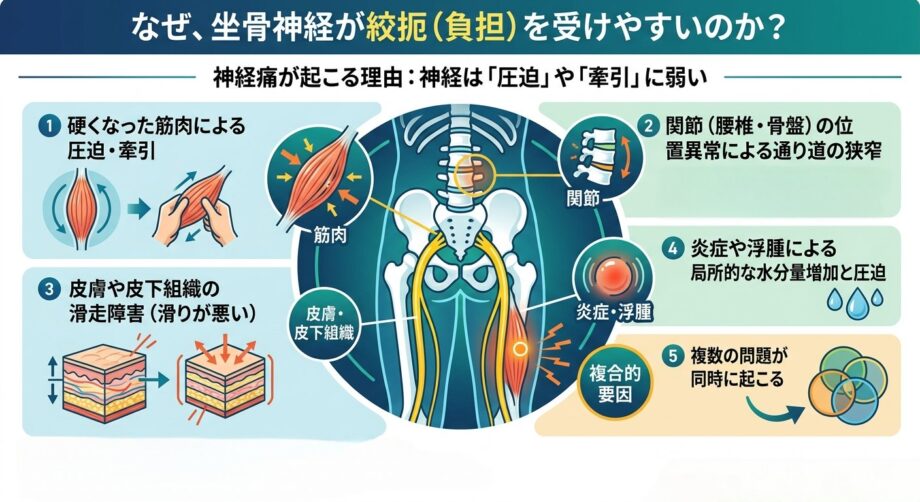

なぜ、坐骨神経が絞扼(負担)を受けやすいのか?

坐骨神経に問題が出やすいのは、いくつか理由があります。

その前に、そもそも神経痛が起こる理由から先にお伝えしておきますね。

神経は圧迫されたり、牽引される力に弱いとされています。

圧迫や牽引されるのは以下の理由が考えられます。

神経が圧迫・牽引を受ける理由

・硬くなった筋肉によって圧迫・牽引される。

・関節(腰椎や骨盤の位置異常)の動きが悪くなることで、神経の通り道が狭くなる。

・皮膚や皮下組織の滑りが悪くなる(滑走障害)

・炎症や浮腫により、局所的な水分量が多くなり、圧迫が加わる。

・複数の問題が同時に起こる。